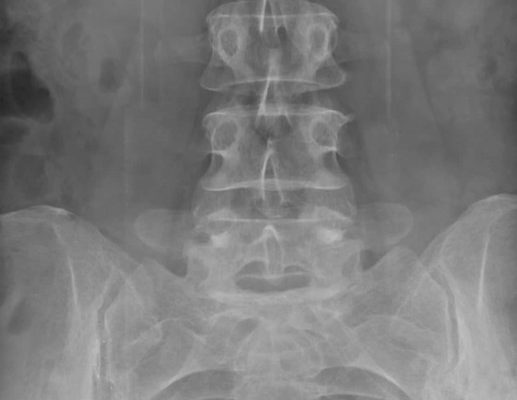

Пациентам, которые жалуются на боли в пояснично-крестцовом отделе позвоночника, проводят рентгенографию копчика. Дискомфорт возникает как после травмы, так и независимо от нее, как следствие патологии опорно-двигательного аппарата. Узнать, почему возникают проблемы с копчиком, поможет рентгенологическая диагностика.

Что покажет рентгеновский снимок

Рентгенологическое исследование помогает визуализировать аномалии, которые невозможно увидеть невооруженным глазом. О травмах копчика можно только догадываться, но окончательный диагноз можно поставить только на основании множественных проекционных рентгенограмм. Показ данных скрининга

• вывих элементов в крестцовой области;

• трещины;

• остеохондроз;

• кисты;

• растяжение связок;

• ушиб;

• воспалительные процессы;

• метастазирование опухоли;

• остеомиелит;

• деформации;

• вспышки остеопороза.

В большинстве случаев врачи ставят диагноз на основании результатов рентгенологического исследования. Например, перелом копчика хорошо виден и не оставляет сомнений. Если врач не удовлетворен результатами обследования, поскольку предполагаемая патология не была выявлена ​​на рентгеновском снимке, он порекомендует альтернативные методы диагностики.